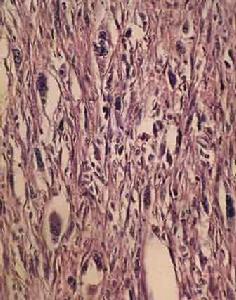

病理

肺表面廣泛分布的囊腫是由擴張的淋巴管在肌層和壁層胸膜上形成類似肺大泡病變所致。新生的不典型平滑肌細

淋巴管平滑肌瘤上述異常增殖的平滑肌細胞其細胞學形態特殊,基因表形呈異質性。在LAM結節內可見三種不同的細胞型:較大的類上皮細胞位於結節外周,而較小的細胞居於中心。除形態學不同外,LAM細胞可套用抗人黑色素瘤抗體(HMB-45)和金屬蛋白酶(MMPs)染色顯示不同的免疫表型。在這些細胞記憶體在不同的蛋白顆粒:平滑肌特異性α-肌動蛋白、波形蛋白和結蛋白顯示不同的免疫組化染色反應提示平滑肌起源的異質性。在電鏡下,LAM細胞也與通常的平滑肌細胞不同。細胞核呈圓形或橢圓形、多切跡、核仁明顯、內含微絲狀物基質成分形成的緻密體和發育良好的內質網。由許多電子密度的膜結合顆粒構成細結晶狀層狀體。相似的細胞也見於腎、肝的血管平滑肌脂肪瘤和肺的透明細胞瘤、LAM細胞異質性使人們構想LAM的發病機制可能與血管或脈管相關的細胞類型似腫瘤樣異常分化與增殖有關。HMB-45是從黑色素瘤雜交瘤提純的一種單克隆抗體。病理學用於惡性黑色素瘤的診斷。在LAM細胞中呈陽性染色。HMB-45與兩種靶蛋白10kD的糖蛋白(Pmel17和GP100)結合。HMB-45陽性見於惡性黑色素瘤和其它細胞線來源的黑色素瘤,如LAM、血管平滑肌脂肪瘤和透明肺腫瘤以及結節性硬化症綜合徵(TSC),提示它可能來源於共同的前體產生的交叉反應。HBM-45曾用於組織學已知證實的5例LAM,均呈陽性結果,而15例原發性自發性氣胸、肺氣腫、Langerhan組織細胞增生症和IPF則均示陰性結果。